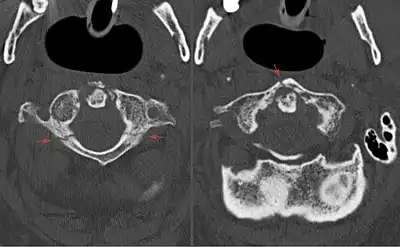

A Jefferson fracture is a bone fracture of the anterior and posterior arches of the C1 vertebra,[1] though it may also appear as a three- or two-part fracture. The fracture may result from an axial load on the back of the head or hyperextension of the neck (e.g. caused by diving), causing a posterior break, and may be accompanied by a break in other parts of the cervical spine.[1]

Diagnosis